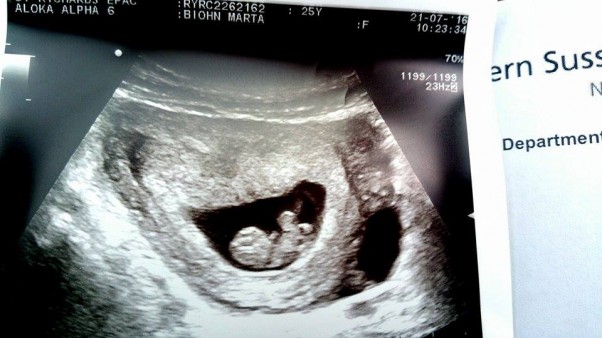

Jesteśmy po kolejnym scanie, przez 3 tygodnie maleństwo urosło jak na drożdżach! :D

Zobaczyłam bijące serduszko, główkę, maleńkie rączki i nóżki. Przy badaniu były 3 kobiety, wszystkie zachwyciły się że mały jest tak fotogeniczny :D

8 tydzień Ciąży , 22 mm :)